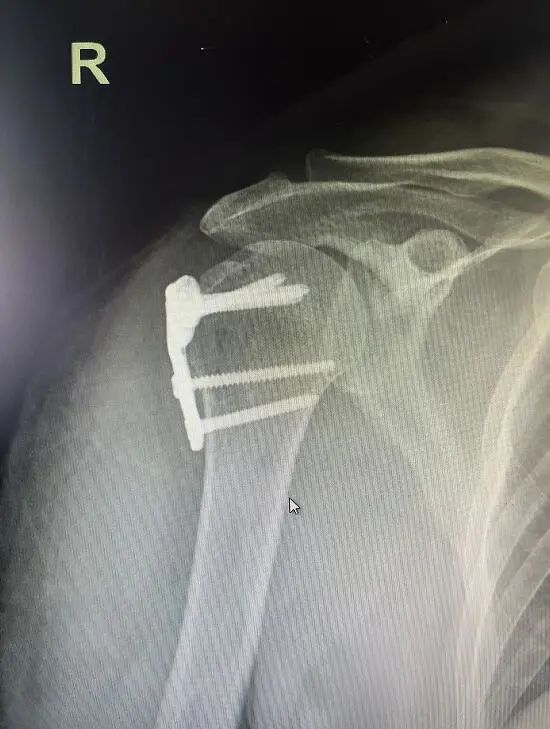

张女士因为摔伤致右肩部肿痛伴功能受限5天入院。入院前患者先后于某市人民医院、某红十字医院住院治疗,症状未见改善,右肩剧烈疼痛,功能活动受限。后经朋友介绍转入我院骨伤科治疗,住院期间拍片提示右肱骨大结节骨折,骨折断端错位明显,具有确切手术指征,完善术前检查后,择期行右肱骨大结节骨折切开复位内固定手术治疗,术后指导患者行右肩关节功能锻炼。现患者已治愈出院,右肩已无疼痛,手术切口愈合良好,右肩关节功能活动正常。